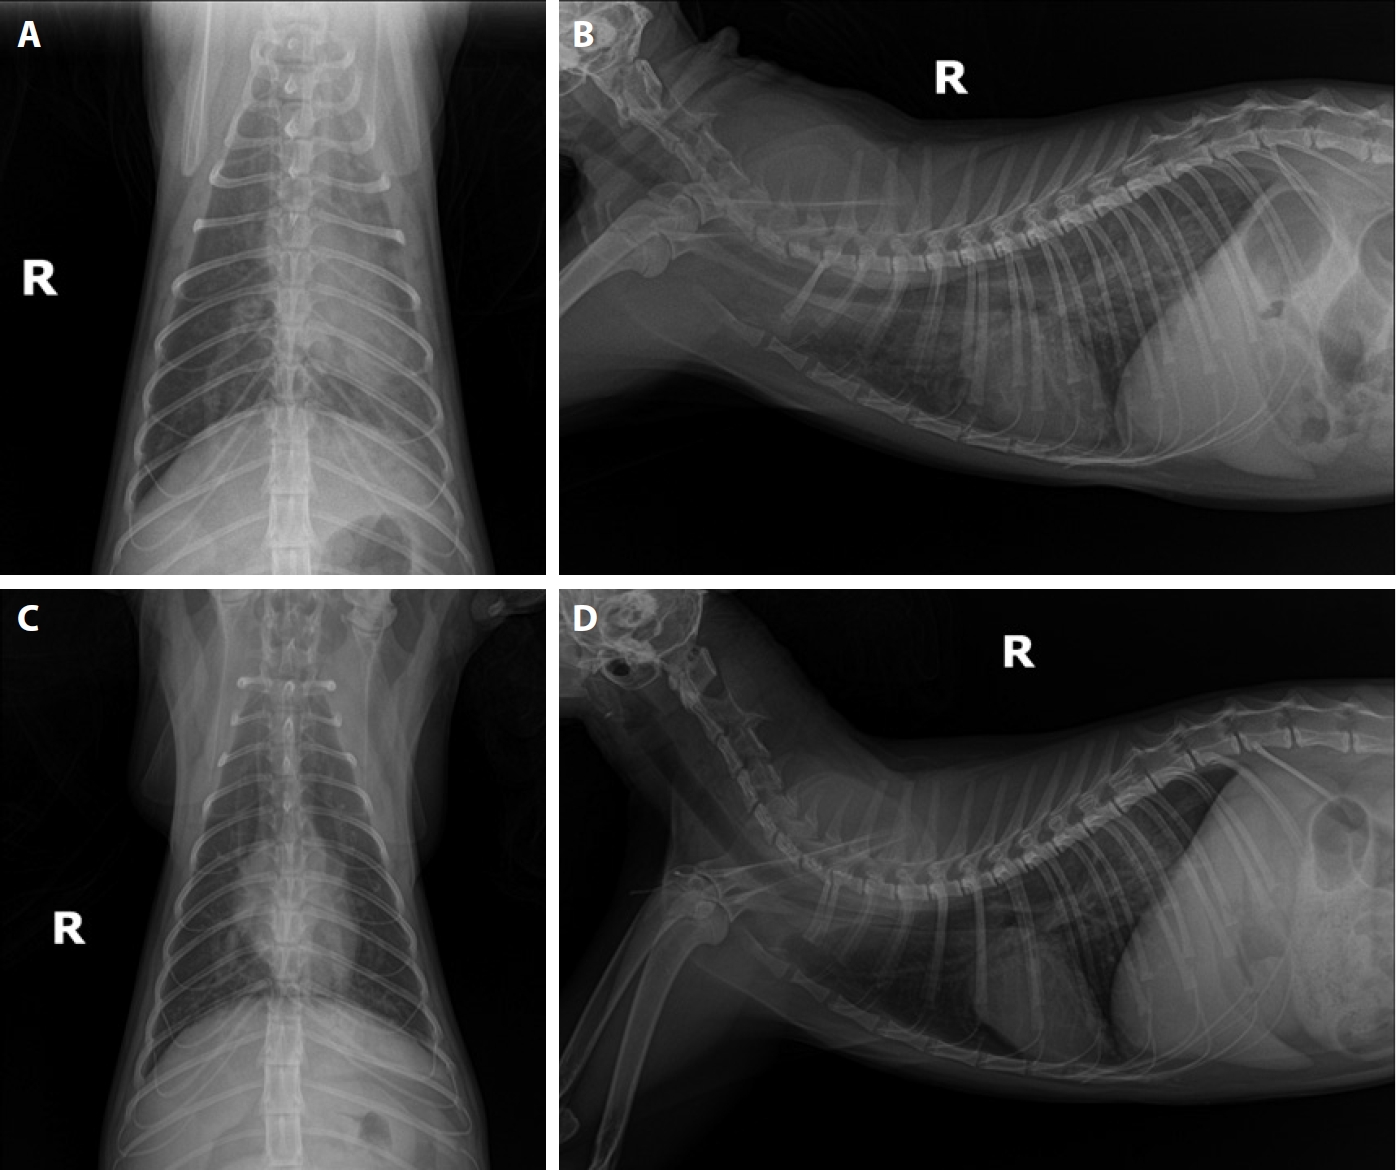

Fig. 2.

Echocardiographic findings in Case 2. (A, B) B-mode image showing multiple hyperechoic, parallel double lines (white arrows) within the bifurcation of the main pulmonary artery (PA) and branches of the right PA, consistent with intraluminal adult heartworms. (C) Right parasternal short-axis view at the level of the aortic root showing a left atrium (LA)-to-aorta (AO) ratio of 1.36, indicating no overt left atrial enlargement. (D) M-mode echocardiography demonstrating normal left ventricular wall motion and systolic function (fractional shortening: 56.3%).

A 5-year-old rescued female stray cat presented with generalized skin ulcers, maggot infestation, and cachexia in August 2019. CBC, serum chemistry, electrolyte analysis, proBNP, FeLV and FIV tests, heartworm antigen and antibody kit tests, thoracic and abdominal radiographs, and abdominal ultrasound were performed. Test results were positive for heartworm antigen and antibody tests, anemia, dehydration, and azotemia. Thoracic radiographs revealed marked dilation and tortuosity of pulmonary arteries coursing through both caudal lung lobes. B-mode echocardiography revealed multiple hyperechoic, parallel double lines within the main pulmonary artery bifurcation and right pulmonary artery branches, consistent with adult heartworms. Standard short-axis, M-mode, and Doppler echocardiography demonstrated a normal left atrium-to-aorta ratio (1.36), preserved systolic function (fractional shortening: 56.3%), and no evidence of severe pulmonary hypertension. These findings confirmed the presence of multiple adult heartworms (Fig. 2).

Case 1 highlights the potential for favorable outcomes with timely and appropriate treatment. Medications considered for feline heartworm disease include prednisolone to relieve coughing and other respiratory signs, doxycycline to eliminate Wolbachia organisms from heartworms that contribute to disease pathogenesis, and supportive therapy such as bronchodilators, oxygen, and fluids to alleviate respiratory distress [6,11,19,20]. With appropriate management, the cat has survived for 4 years following diagnosis and has remained asymptomatic to date. In Case 2, echocardiography played a pivotal role in confirming heartworm infection in this cat, demonstrating characteristic imaging findings. B-mode imaging revealed multiple hyperechoic, parallel double lines in the main and right pulmonary arteries, a pathognomonic sign of adult heartworms. Echocardiography showed normal chamber sizes, preserved systolic function, and no severe pulmonary hypertension, underscoring its value for detecting early or asymptomatic infections and complementing antigen testing.

Fig. 2. Echocardiographic findings in Case 2. (A, B) B-mode image showing multiple hyperechoic, parallel double lines (white arrows) within the bifurcation of the main pulmonary artery (PA) and branches of the right PA, consistent with intraluminal adult heartworms. (C) Right parasternal short-axis view at the level of the aortic root showing a left atrium (LA)-to-aorta (AO) ratio of 1.36, indicating no overt left atrial enlargement. (D) M-mode echocardiography demonstrating normal left ventricular wall motion and systolic function (fractional shortening: 56.3%).